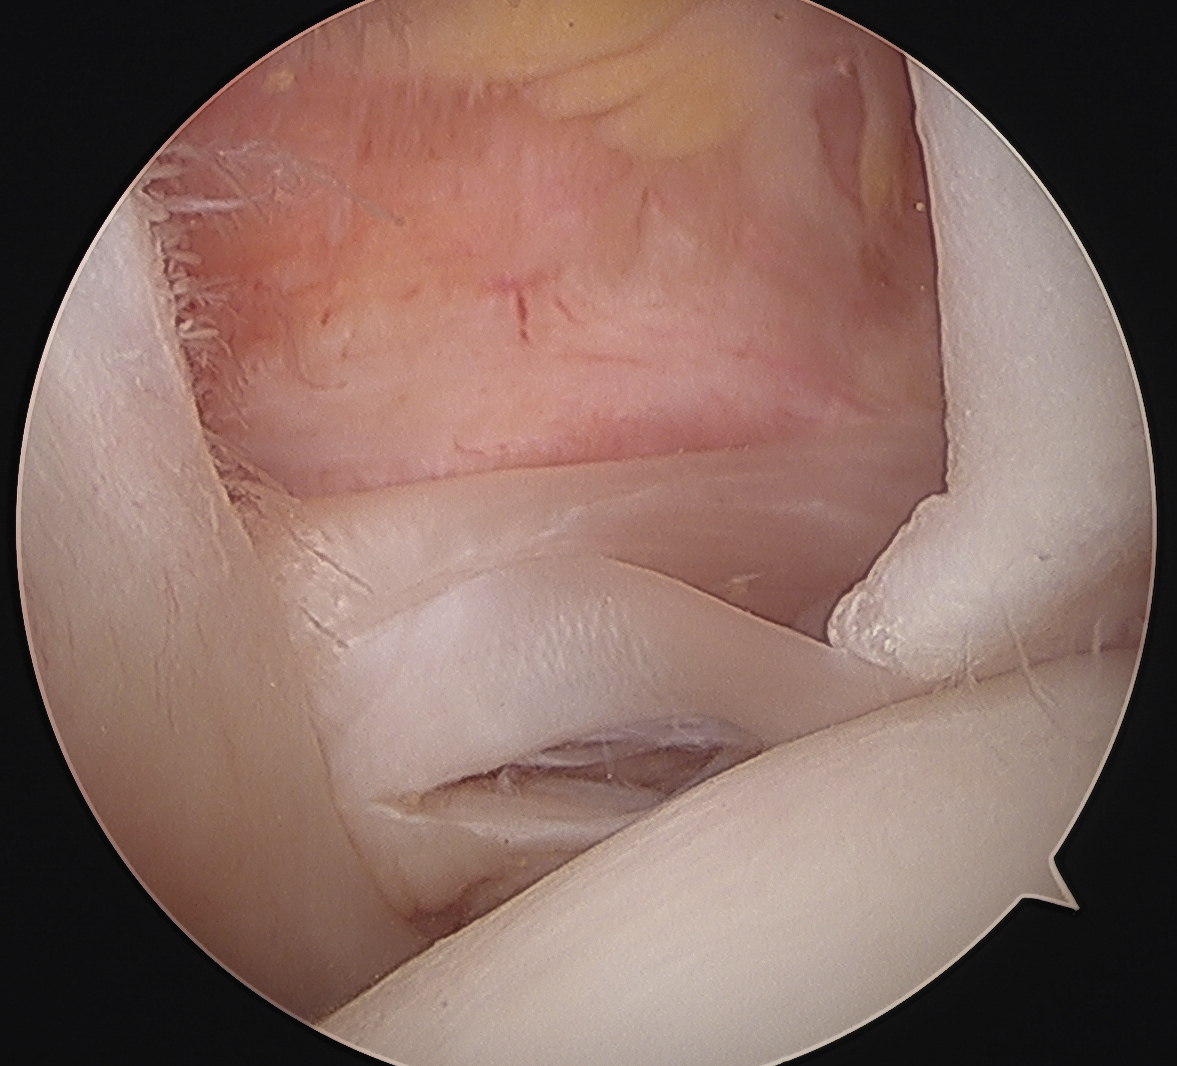

Medially dislocated biceps tendon with upper border subscapularis tear

Full thickness tear of subscapularis off insertion revealed with grasper